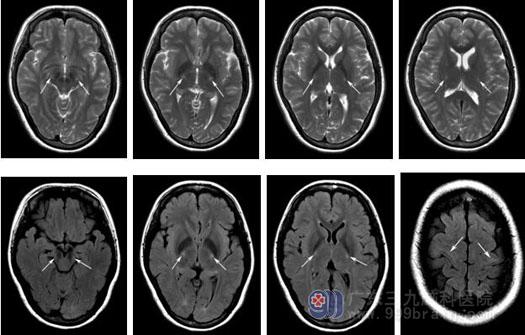

▲神经影像学检查:头颅MRI: 双侧皮质脊髓束、双侧额叶中央前回皮层下白质对称性T2WI及FLAIT序列异常高信号。

ALS最早期的MRI特征为皮质脊髓束在T2WI上呈高信号,这种信号改变起始于内囊,逐渐累积脊髓,造成脊髓萎缩、体积缩小,此外运动皮层异常的铁沉积和神经退行性改变使中央前回皮层在T2WI和T2*WI呈线状低信号。该患者头颅MRI发现了对称的皮质脊髓束损害。累及皮质脊髓束的疾病谱,工作中第一个想到的病就是ALS。既往我们在工作中只关注ALS患者的电生理检查,而忽略了头颅MRI对称的皮质脊髓束也是ALS的一个重要临床表现。有MRI皮质脊髓束损害的患者,症状进展更快,病程更短。在以后的临床工作中,如果遇到类似患者,当电生理尚未达到ALS诊断标准(3个部位的上、下运动神经元病变证据)时,而MRI提示了对称的双侧皮质脊髓束损害时,应该高度怀疑ALS,做到早期诊断。